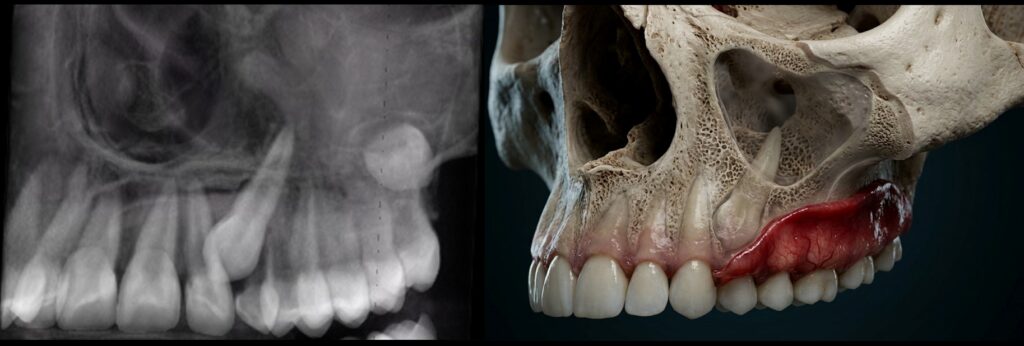

What if I told you that in just two days you could learn a repeatable, radiologist-level workflow to confidently diagnose vertical root fractures, recognize extra-radicular infections, and interpret advanced CBCT findings that many clinicians miss—especially when artifacts make the scan “look unreadable”? Now imagine doing that in beautiful Santa Barbara, California. Picture reviewing a CBCT scan like the one below—streaking, scatter, motion, and metal artifacts obscuring the details that matter most. Instead of guessing, you’ll know exactly what to look for, how to use MAR vs. BAR filtering appropriately, and how to make a confident call when the findings are subtle. By the end of this hands-on course, you’ll be able to read challenging cases with clarity, improve clinical decision-making, and communicate your findings more effectively to your team and referring doctors.